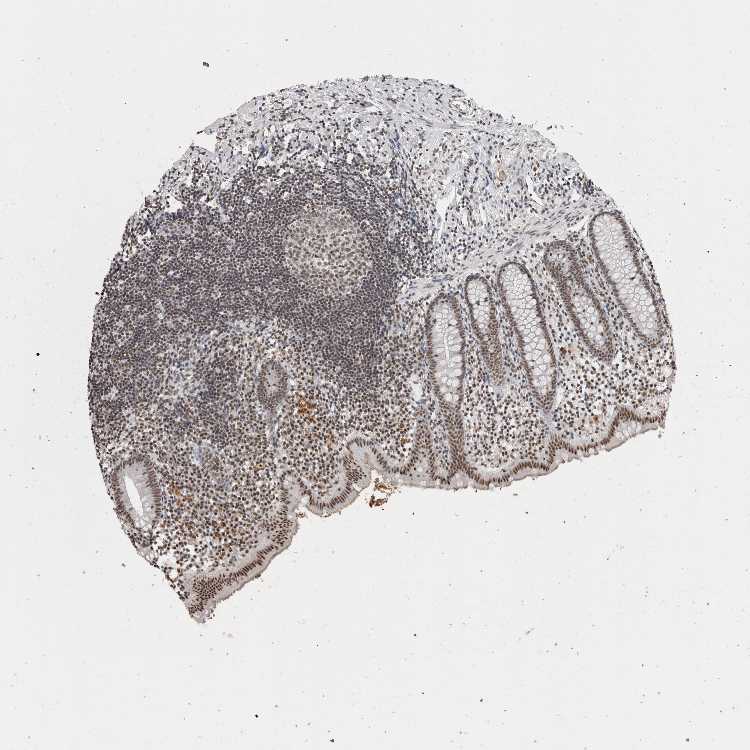

APPENDIX - Expression summary

Appendixi

On the top, protein expression in current human tissue, based on all annotated cell types, is reported with the units not detected (n), low (l), medium (m) and high (h). Underneath, protein expression in each annotated cell type are reported using the same units.

Protein expression data is based on knowledge-based annotation. For genes where more than one antibody has been used, a collective score is set.

APPENDIX - Antibody stainingi

Antibody staining in the annotated cell types in the current human tissue is reported as not detected, low, medium, or high, based on conventional immunohistochemistry profiling in selected tissues. This score is based on the combination of the staining intensity and fraction of stained cells.

Each image is clickable and will lead to virtual microscopy that enables deeper exploration of all samples and also displays staining intensity scores, fraction scores and subcellular localization as well as patient and tissue information for each sample.

Antibody HPA063142Antibody CAB024908

Glandular cells MediumMedium

Lymphoid tissue LowMedium